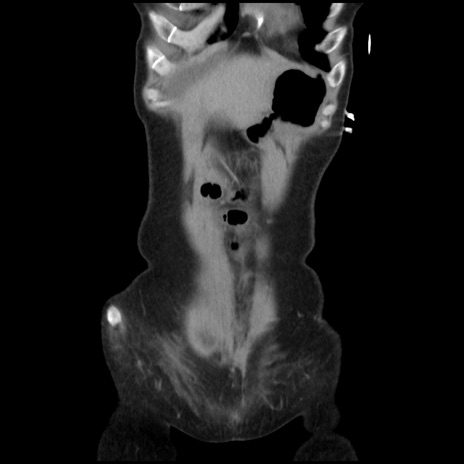

矢状断像